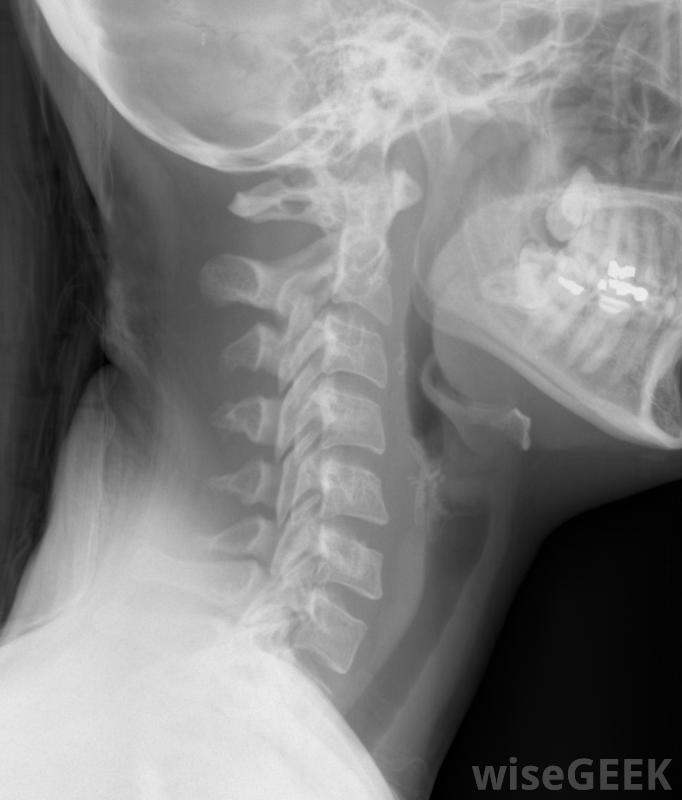

頸椎椎板切除術,有時也被稱為頸椎后路椎板切除術,是對頸椎進行的幾種可能的手術之一。頸椎由脊柱區域的七個椎板組成。這種手術允許外科醫生切除部分椎板椎板切除術是為了減輕對脊髓和周圍神經的壓力如果脊髓受壓,這通常是由于年齡增長而導致的,則可以進行脊髓手術。接受這種手術的病人經常因為持續的頸部疼痛而去看醫生。他們也可能會感到手臂以下刺痛或麻木,發燒,或者失去協調性。在考慮手術之前,患者應該先嘗試更保守的治療方法。這些方法可能包括臥床休息、物理治療,椎板切開術是為了減輕脊髓的壓力如果保守治療方法失敗,患者應與醫生仔細討論手術。頸椎椎板切除術的準備工作將在手術前兩周開始。患者應向外科醫生披露所有藥物和其他醫療狀況有些藥物可能會增加出血的風險,因此外科醫生可能會建議患者在手術前停止服用如果病人正在服用止痛藥治療頸部疼痛,他可能需要在手術前減少劑量或停止服用。這可以提高患者在手術后恢復期間服用止痛藥的有效性。吸煙患者需要在手術前至少24小時內禁煙。這是為了讓患者做好麻醉準備。此外,手術前一晚午夜后,患者將無法進食或飲水。

頸椎椎板切除術是對頸椎進行的幾種可能的手術之一在開始頸椎椎板切除術時,外科醫生首先要在脊椎上切開一個切口,然后用x光片確認每一個椎體的正確性,然后醫生可以取出椎板,以及任何可能壓迫神經的骨刺或其他外來物質。在某些情況下,外科醫生會在椎板上切開并折疊起來,而不是完全切除。在去除所有必要的材料后,外科醫生可以將切口縫合在一起在頸椎椎板切除術后恢復過程中,患者可能需要佩戴頸托。這將在該區域愈合時保持頭部靜止。具體所需的恢復時間因患者而異。外科醫生會建議患者何時可以恢復工作和其他正常活動。有些患者可能會進行身體鍛煉手術后的治療。如果手術中出現任何并發癥,患者可能需要額外的治療。頸椎椎板切除術的一些可能的并發癥包括感染、出血,病人在手術前應仔細考慮是否有脊髓損傷或神經損傷的獨特情況。有時也要注意病人是否有脊髓損傷或神經損傷進行頸椎椎板切除術。